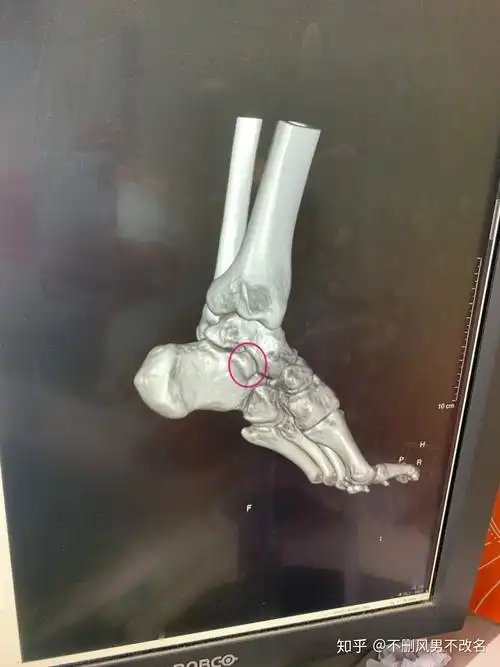

脚踝扭伤一年了,有轻度增生 - 知乎